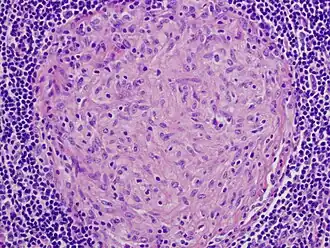

![]() Микроскопическая картина гранулёмы в лимфатическом узле (инфекция Mycobacterium avium). | |